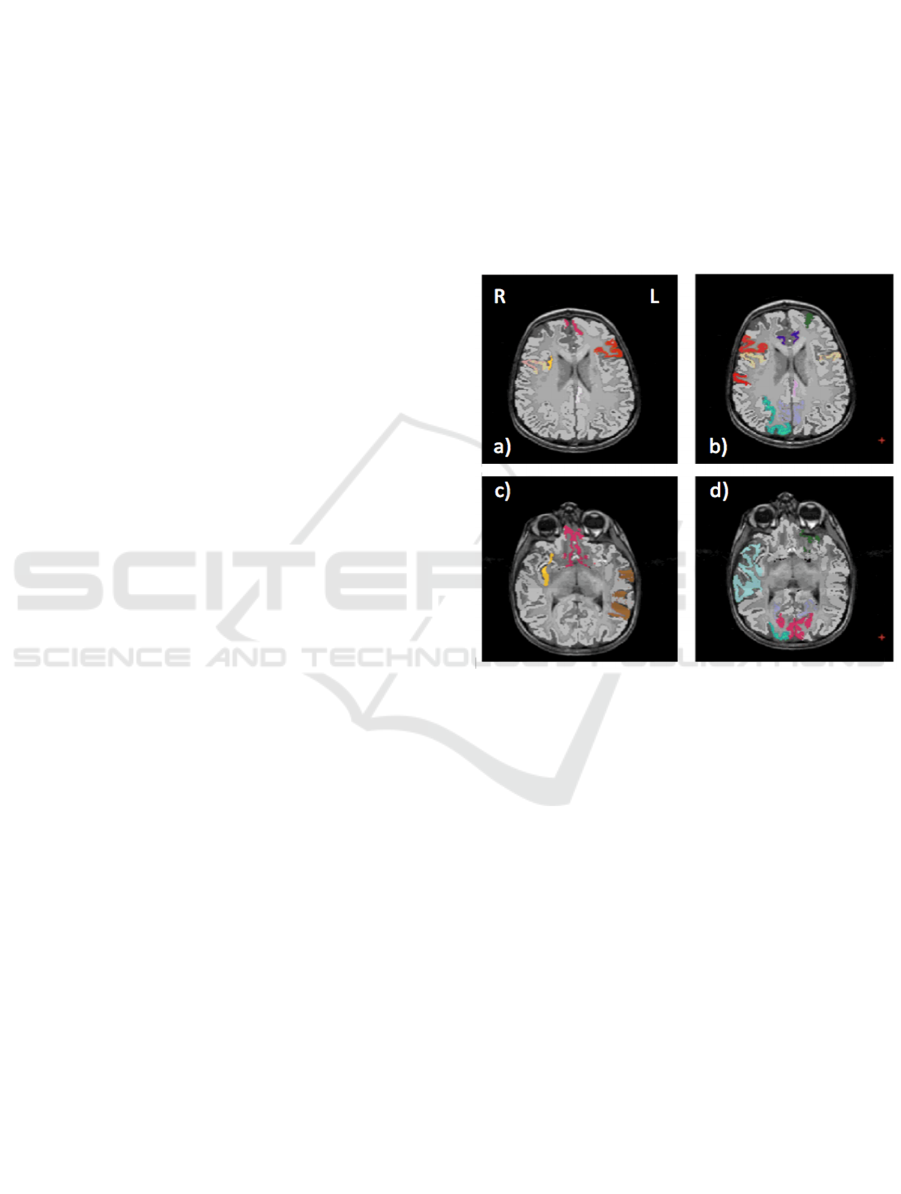

We show in Figure 2 the brain regions most

contributing to the definition of the OCC boundary,

as resulting from the permutation test, for male and

female subsets, respectively. For the male

population the regions visible in Figure 2(a,c) are:

left (L) and right (R) medial orbito frontal cortices,

L pars triangularis, R pars opercularis, middle

temporal cortex and R insula. For the female

population the regions visible in Figure 2(b,d) are: L

and

R caudate anterior cingulate, pars opercularis,

posterior cingulated, cuneus; R pars triangularis

postcentral gyrus, superior temporal cortex and

superior parietal cortex. They are mostly among the

network of structural brain alterations widely

reported in the population with ASD, including

frontal and temporal areas.

Figure 2. Brain region most contributing to the definition

of the OCC boundary. For the male population the regions

visible in a) and c) are: left (L) and right (R) medial orbito

frontal cortices (pink), L pars triangularis (red), R pars

opercularis (mustard), middle temporal cortex (brown) and

R insula (yellow). For the female population the regions

visible in b) and d) are: L and R caudate anterior cingulate

(violet), pars opercularis (mustard), posterior cingulate

(light violet), cuneus (magenta); R pars triangularis and

postcentral gyrus (red), superior temporal cortex (light

blue), superior parietal cortex (cyan).